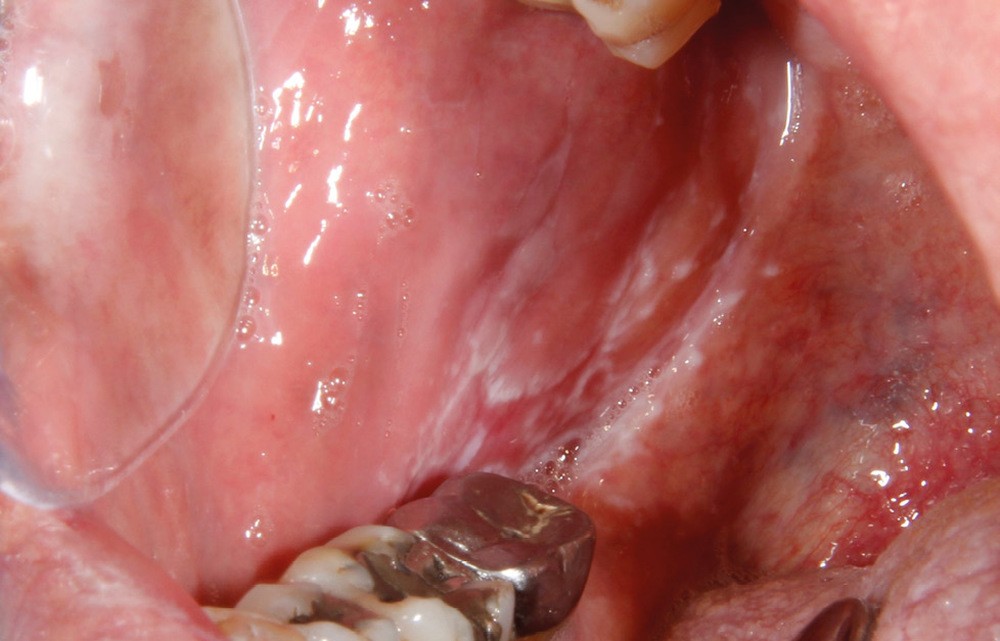

À l’interrogatoire, le patient affirme qu’il a des difficultés à maintenir une hygiène bucco-dentaire satisfaisante du fait des douleurs, et n’a pas pu consulter son chirurgien-dentiste pour son détartrage annuel en raison de la crise sanitaire en cours. L’examen clinique révèle une parodontite chronique (stade 3) généralisée et des lésions jugales (fig. 1 et 2), labiales (fig. 3) et gingivales (fig. 4) érythémateuses et kératosiques. Les lésions kératosiques jugales sont de type réticulé (fig. 1 et 2) ; les lésions kératosiques labiales sont associées à de petites érosions (fig. 3) ; les lésions palatines à des ulcérations (fig. 5). La langue présente une lésion blanche en « tache de bougie » (fig. 6) ; la muqueuse du plancher buccale est saine (fig. 7). Le signe de la pince est négatif. Le patient n’est pas porteur de prothèse dentaire malgré un édentement de moyenne étendue. Aucune lésion cutanée ou génitale n’est rapportée par le patient.

Le diagnostic le plus probable est le lichen plan (LP). On note, au niveau jugal, une kératinisation en réseau marquée par les stries de Wickman. Un phénomène de Koebner (exacerbation…